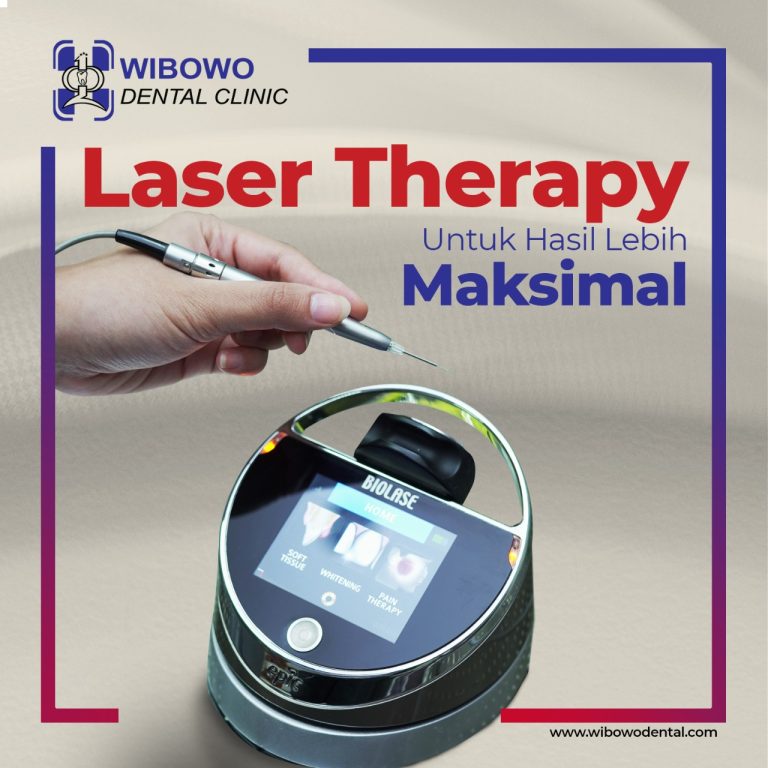

Eksis sejak tahun 1978, Wibowo Dental Clinic merupakan pionir Digital Dentistry di Surabaya. Mengedepankan perawatan yang terintegrasi dari tim dokter spesialis periodonsia, orthodonsia, dan konservasi gigi dan pengaplikasian teknologi terkini, Wibowo Dental Clinic telah dipercaya oleh berbagai kalangan, termasuk tokoh nasional.